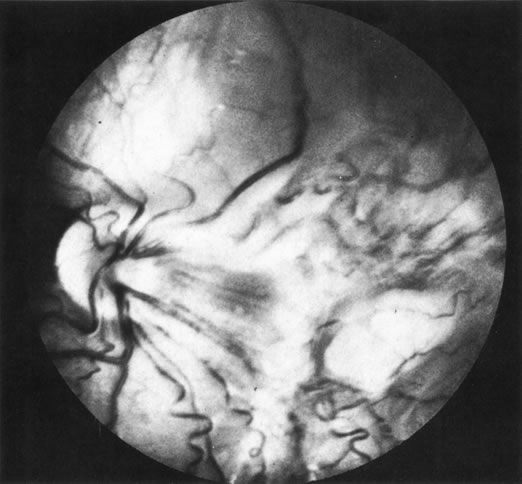

Necrotic melanomas account for approximately 5% of uveal melanomas; in the majority of cases, there is intraocular inflammation accompanying the cataract.7–9Figures 1 and 2 demonstrate a typical case. The patient had a long history of unilateral decreased vision. The eye had become painful 1 month before admission, and he was referred for evaluation of uveitis. Clinically, there was a dense, unilateral cataract with significant intraocular inflammation, which was manifested as a ciliary flush with 2+ cells and flare. Media opacity obscured all fundus detail. An immersion B-scan demonstrated a large intraocular tumor that was most consistent with a uveal melanoma. The eye was removed, and the diagnosis was confirmed histologically.10

Fig. 1. A unilateral media opacity in an adult, requiring that either a foreign body or an intraocular tumor be ruled out. The finding of a large episcleral (“sentinel”) vessel was consistent with either an intraocular tumor or an inflammation. An immersion B-scan helped determine the diagnosis (see Fig. 2).